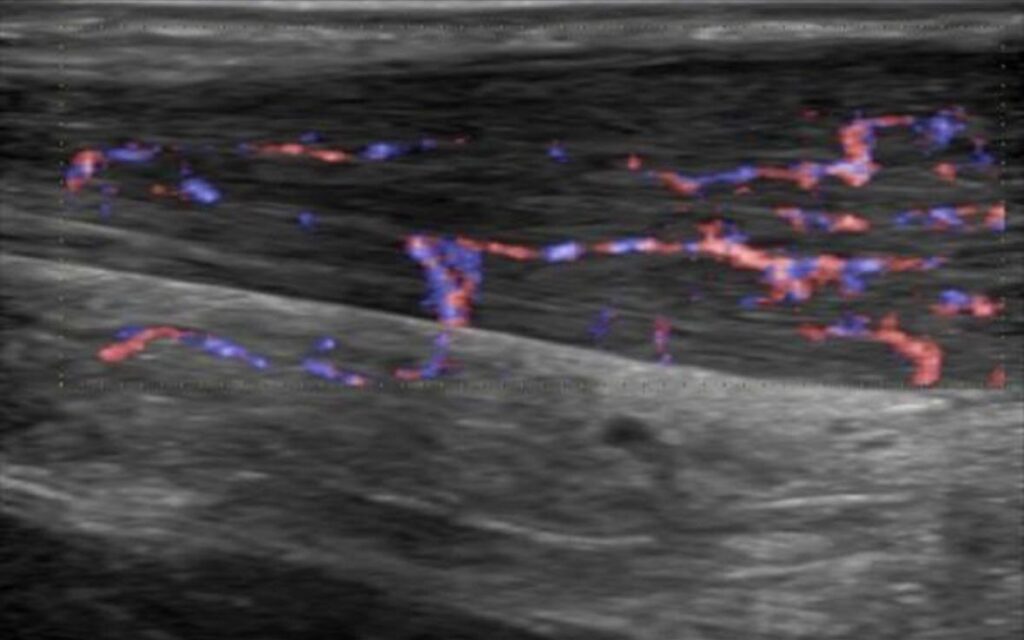

Tendinopatía del tendón de Aquiles

En esta imagen muestra un tendón de Aquiles engrosado. Mientras que la parte de la izquierda (proximal) mantiene un tamaño normal, la parte de la derecha (distal) el tendón se abomba.

Ese engrosamiento difuso es un signo típico de las tendinopatías, que en este caso el paciente sufría desde hacía 1 año. Igualmente, la imagen muestra neovascularización asociada a la tendinopatía del tendón de Aquiles.